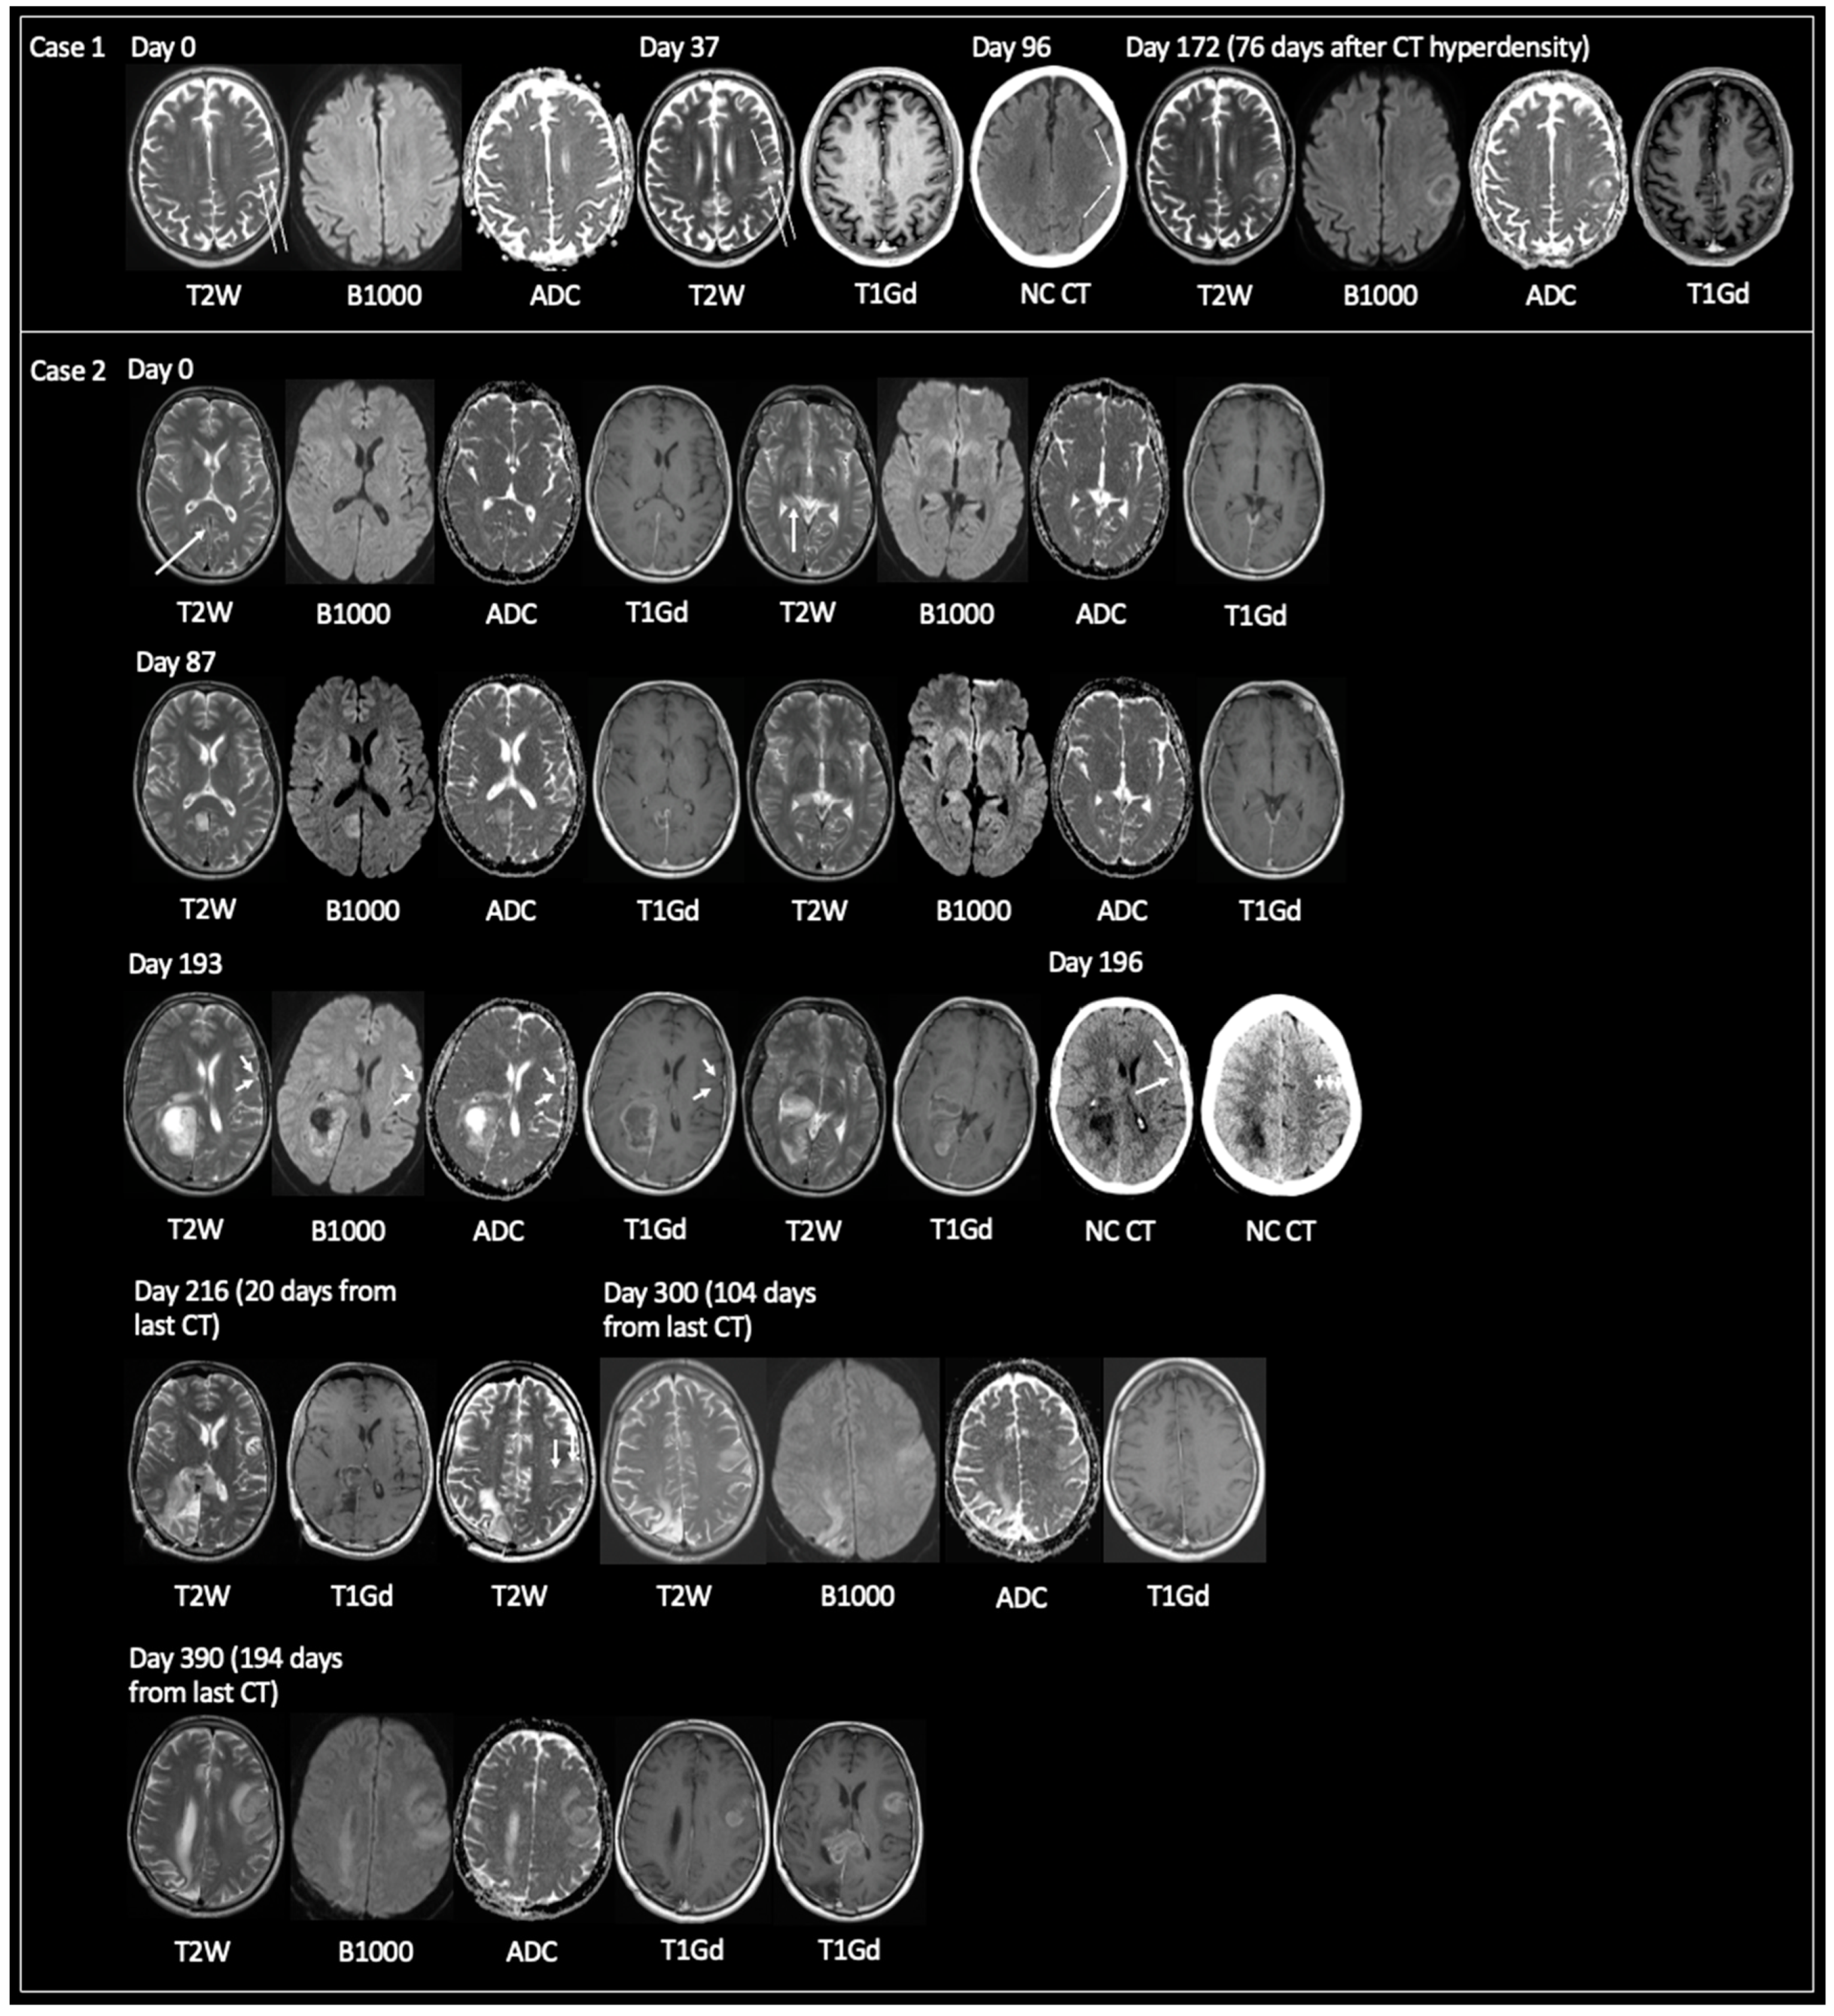

3.1.1. Non-Typical GBM at Time of Tissue Sampling

3.1.2. TRA GBM with Preceding Imaging